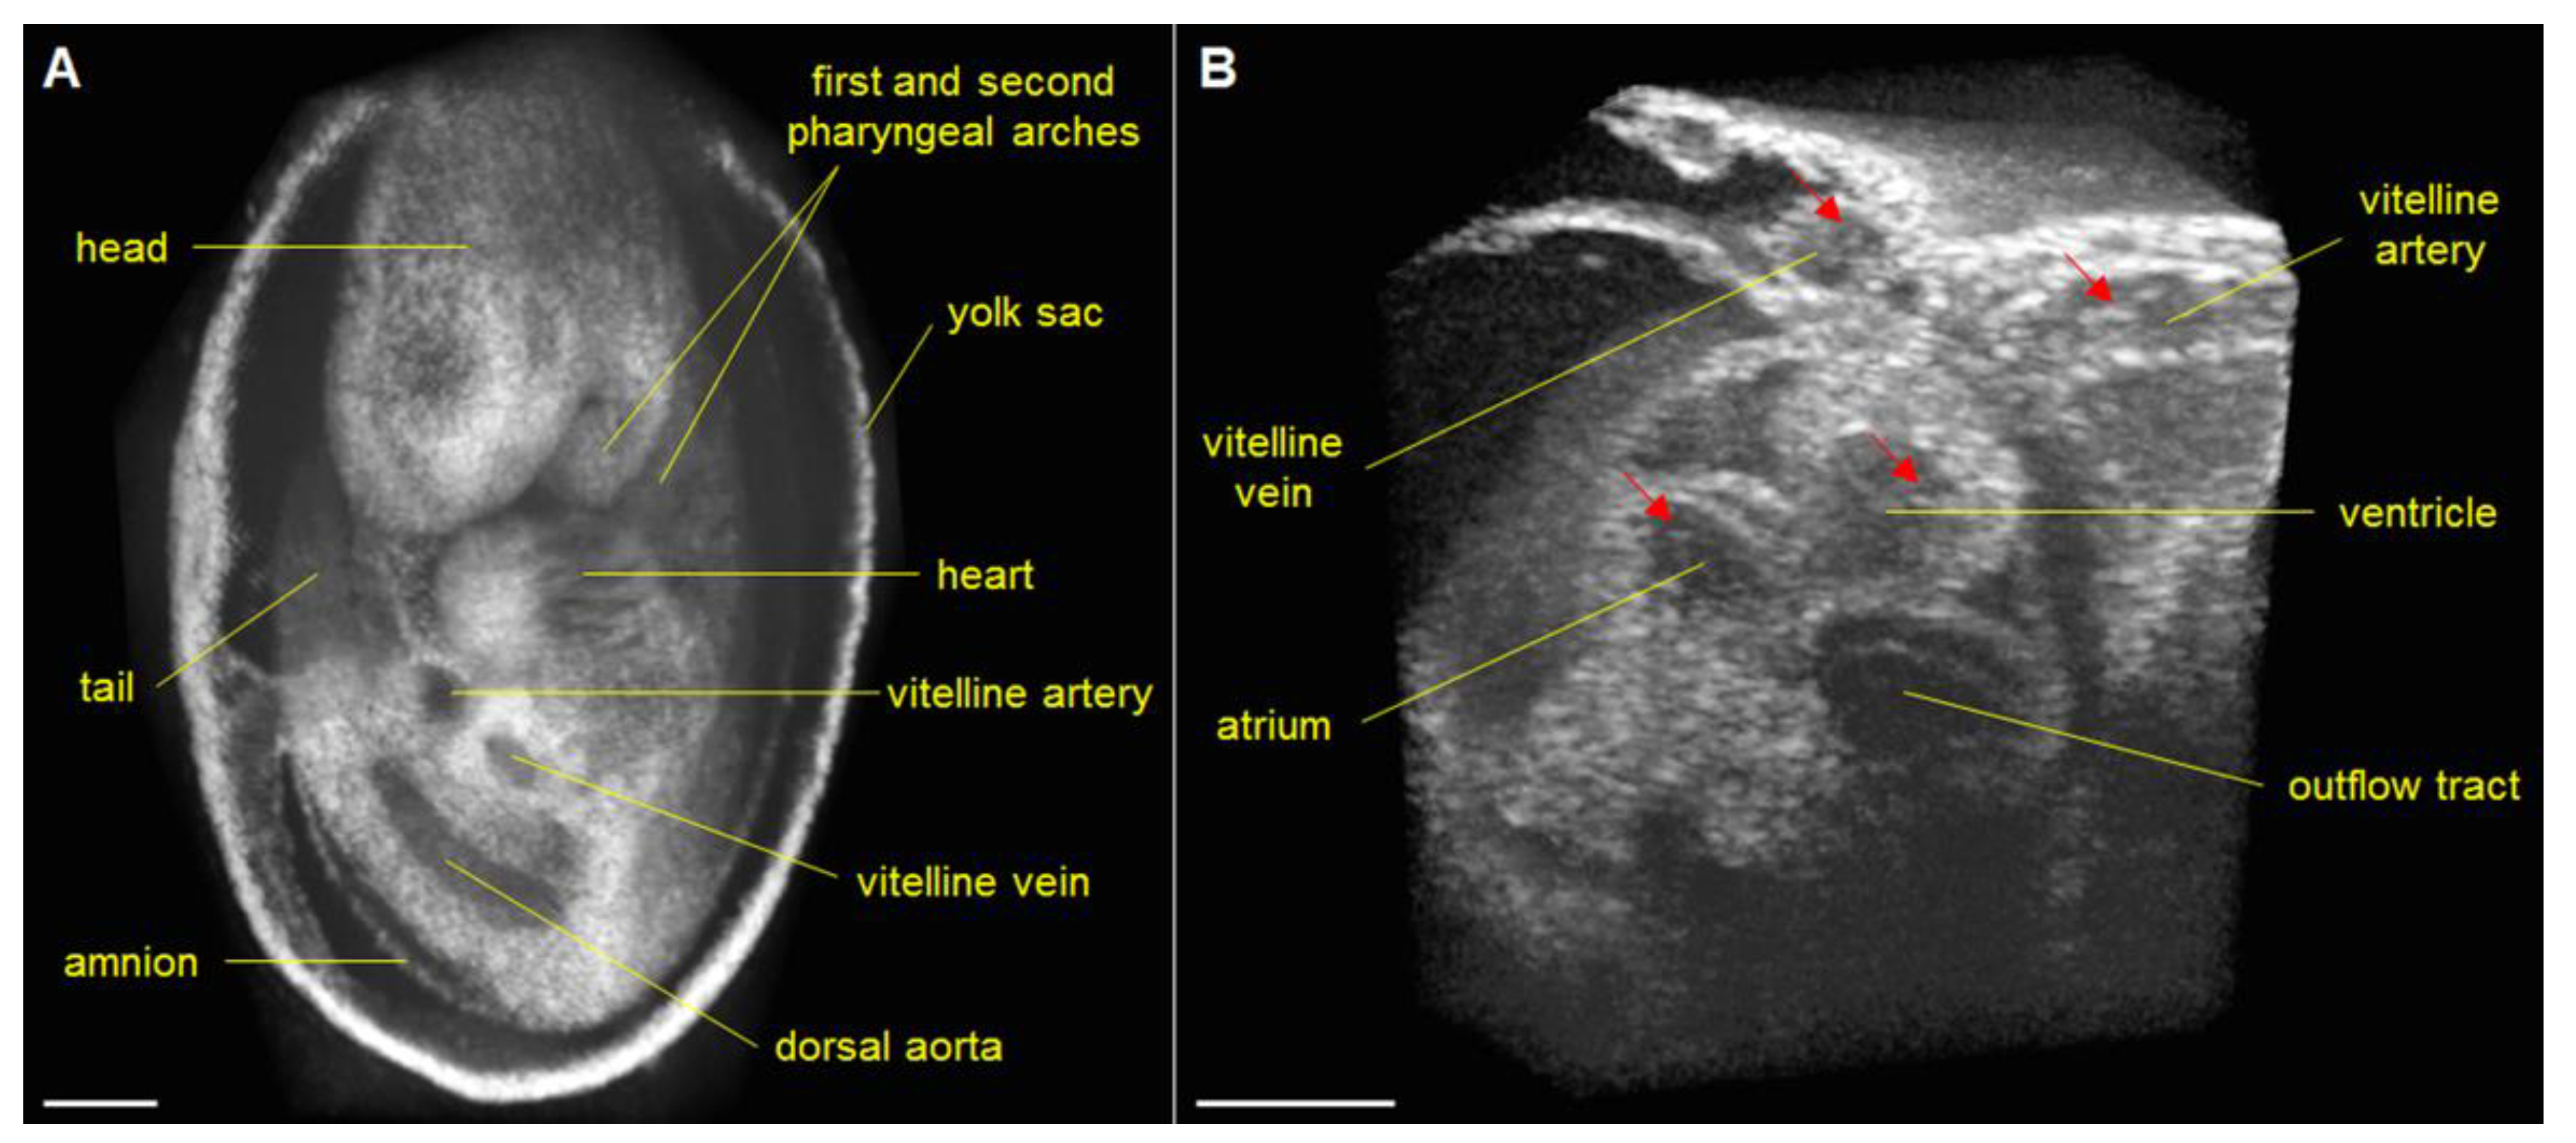

4. Cardiac Phenotyping of Genetic Mouse Models

5. Hemodynamic Imaging with Doppler OCT

- Wang, S.; Lakomy, D.S.; Garcia, M.D.; Lopez, A.L.; Larin, K.V.; Larina, I.V. Four-dimensional live imaging of hemodynamics in mammalian embryonic heart with Doppler optical coherence tomography. J. Biophotonics 2016, 9, 837–847. [Google Scholar] [CrossRef] [Green Version]